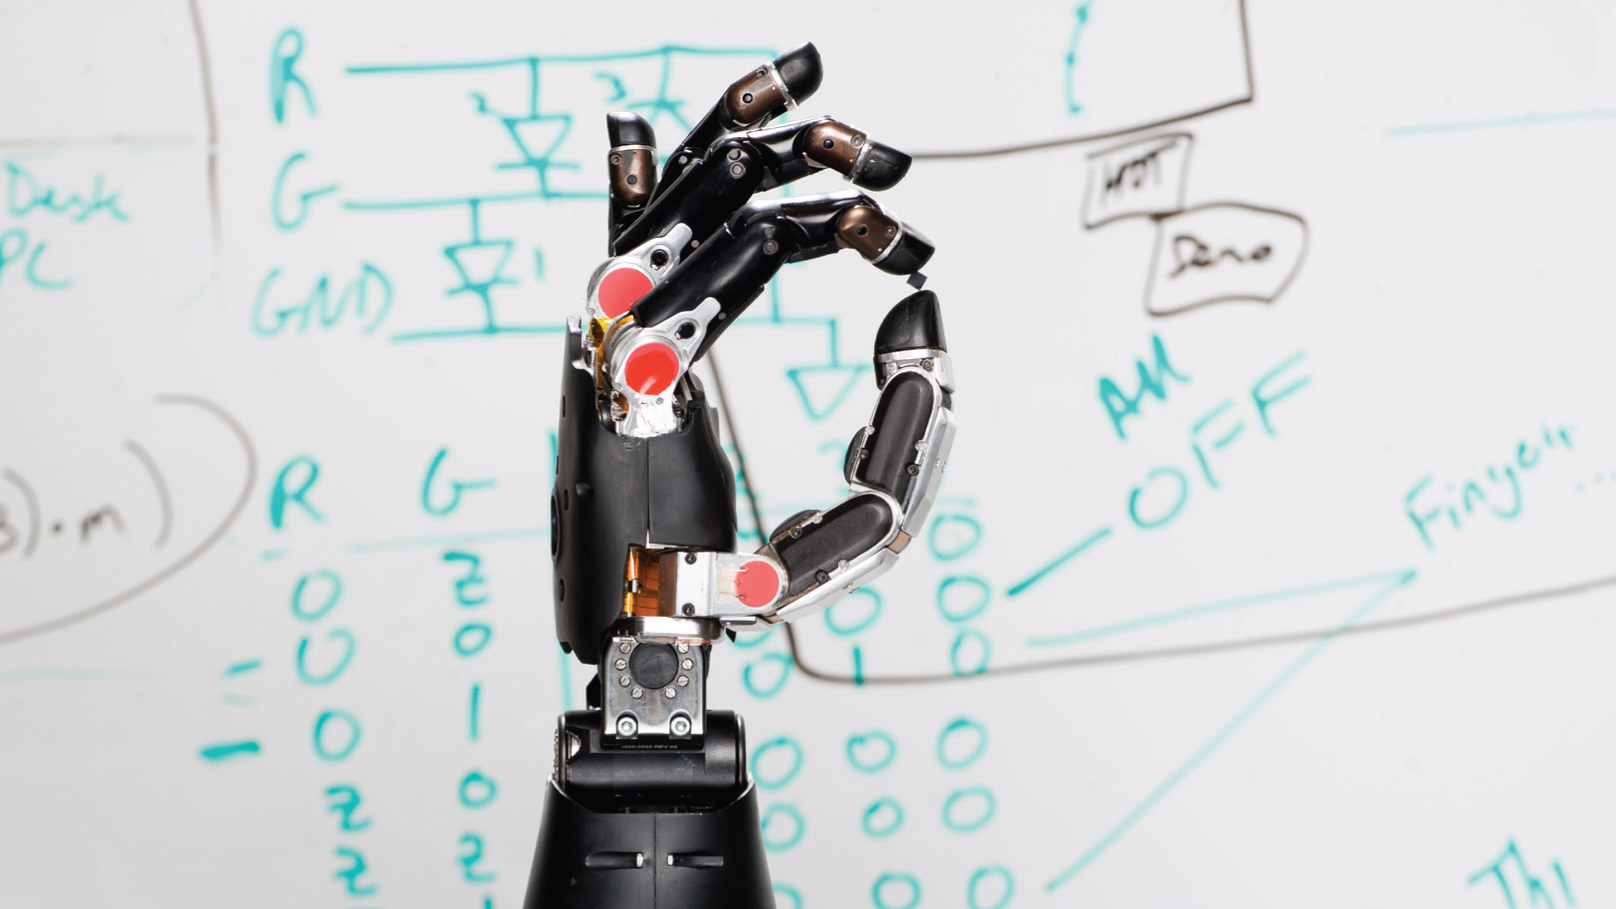

Advances in brain-machine interfaces are leading to incredible treatments, like this prosthetic arm that is controlled through thought.

If you know someone with severe neurological damage — perhaps cerebral palsy, trauma from a car or motorcycle accident, a military or sports injury, or a stroke — you’ve seen, firsthand, how communicating with the outside world and performing daily tasks can be a challenge. But during the past few decades, scientists have made impressive progress in developing technologies that can bypass such damage. Now brain-machine interfaces can read the activity of millions of neurons — through electroencephalographic (EEG) activity from the brain’s surface or from implanted electrodes — and predict the behavioral intentions of research participants. These advances give human and animal subjects neural control of parts of their surroundings: from computer cursors to video games to robotic limbs.

The clinical applications of brain-machine interfaces quickly became clear. Neuroscientists and surgeons implanted electrode arrays in the brains of patients with epilepsy, paralysis, stroke, or Lou Gehrig’s disease (ALS), in hopes of enabling them to communicate and, someday, move independently. In early experiments, patients were only able to gain rudimentary control of a computer cursor. But a breakthrough occurred in 2011 when, after months of extensive training, quadriplegic patients learned to control movements of a third (robotic) arm — enabling them to grasp a drink of water or reach out to a loved one.

Honing this technology is allowing patients to control their own paralyzed limbs. Electrode chips implanted in their brains are connected to sleeves or gloves worn over the injured limbs. Sending tiny blasts of electricity into the patient’s nerves, located under the sleeve or glove, can reanimate paralyzed muscles. But brain-machine interfaces won’t become part of clinical medicine until they’re simplified, miniaturized, and made more reliable. Devices that wirelessly transmit commands from brain implants are a step in that direction.

A parallel line of research has explored applying this technology in the broader field of neuroprostheses. Neuroprosthetic devices not only receive output commands from a patient’s nervous system, but can also provide input — as occurs in retinal implants and prosthetic limbs. Prosthetic arms, for example, have remained frustratingly low-tech, but some brain-guided prostheses have integrated nerves and muscles at several different levels, allowing users to perform more precise and natural movements, and even enabling some to “feel” again. Still, even the most sophisticated neuroprostheses (such as brain implants) are limited by their number of electrodes and the lifespan of the implanted electrodes. Current arrays can only connect to 100 or so neurons, so a more complex and useful bionic future is still far away. Yet scientists and entrepreneurs are already thinking of new uses for the technology: restoring memory; enhancing cognition; and treating diseases such as depression, Alzheimer’s, and epilepsy.